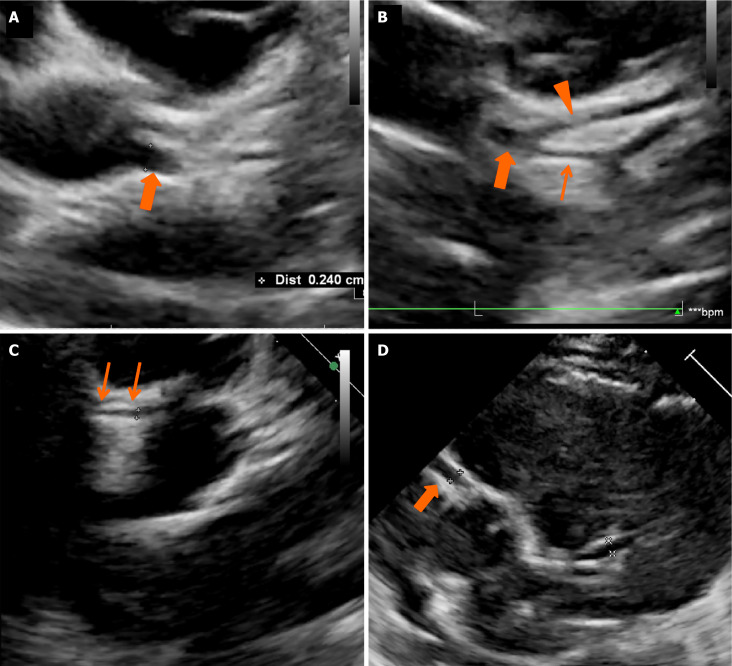

Results: Of the 241 patients with KD who underwent CTCA, 3 (1.24%) had congenital coronary artery anomalies on CTCA detected incidentally. In all 3 patients, baseline 2DE had identified CAAs. CTCA was then performed for detailed evaluation as per our unit protocol. One (11-year-boy) amongst the 3 patients had complete KD, while the other two (3.3-year-boy; 4-month-girl) had incomplete KD. CTCA revealed separate origins of left anterior descending artery and left circumflex from left sinus [misinterpreted as dilated left main coronary artery (LCA) on 2DE], single coronary artery (interpreted as dilated LCA on 2DE) and dilated right coronary artery on 2DE in case of anomalous origin of LCA from the main pulmonary artery. The latter one was subsequently operated upon.